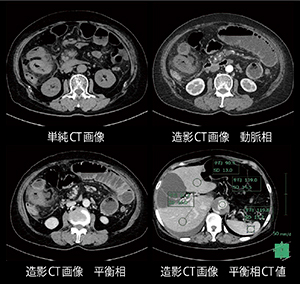

高度腎機能低下患者に対する低管電圧撮影を駆使した緊急造影検査

松本一則(魚沼基幹病院医療技術部放射線技術科)

【背 景】75歳,女性,64kg。腹痛と腹部膨満感を主訴に来院。eGFR23.7,血清クレアチニン1.67と高度の腎機能障害のため,原因検索のCT検査は単純撮影を施行。小腸に広範な壁腫脹と腸間膜に浮腫があり,明らかな閉塞機転は認められなかったが,小腸の一部に高吸収域が存在し虚血もしくは壊死が疑われた。上腸間膜動脈(SMA)の分枝に血栓と思われる高吸収域も認められ,血流障害を来している可能性が示唆された。腎臓内科より可能な限り造影剤を減量するよう指示を受け,造影検査を施行することとなった。

【所 見】上腸間膜動脈は末梢が細いものの明らかな血栓は認めない。上腸間膜静脈(SMV)〜門脈,脾静脈に多量の血栓を認める。小腸の腫脹は血栓によるうっ血〜虚血を見ていると思われる。右側に単純CTで高吸収かつ造影不良な小腸があり,虚血〜壊死疑い。下行〜腹部大動脈に壁在血栓あり。一部に潰瘍性変化あり。単純CTでは上腸間膜動脈の血栓を疑ったが,造影CT検査施行により,門脈・上腸間膜静脈血栓症と診断された。

【訴求ポイント】本症例は可能な限り造影剤量を減量することが命題であった。当院の腹部造影検査では管電圧100kV,使用ヨード量500mgI/kgとしている。一方,大血管のCTAではそれぞれ100kV,400mgI/kgを使用し動脈相と平衡相を撮影しているが,腹部臓器でも100kV,400mgI/kgで得られる造影効果を目標とした。使用管電圧を80kVとした場合,100kV,400mgI/kgと同等な造影効果を得るためには,当院で行った実験結果では400mgI/kg×0.75=300mgI/kgとなる。今回は単純CTの画像より脂肪が多いことが既知であり,詳細は省略するが,除脂肪体重を指標に使用量を算出した結果250mgI/kgとなり,動脈相,平衡相共に良好な造影効果を得ることができた。